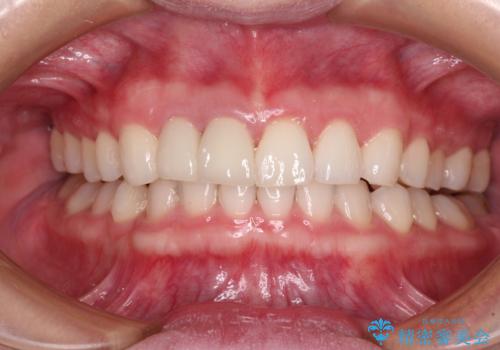

治療前、下顎前歯はほとんど見えない咬み合わせでしたが、矯正治療によりディープバイトが改善されました。

矯正治療中に前歯2本のクラウンは外れてしまい、途中仮歯に替える必要があったので期間は掛かりましたが、歯列も整い、負担のかからない咬み合わせを達成することができました。